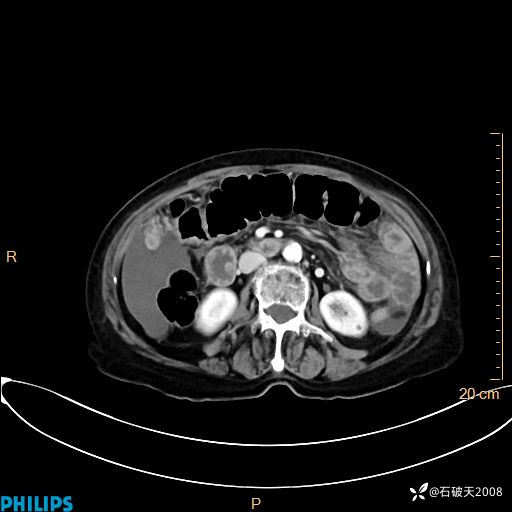

MIP